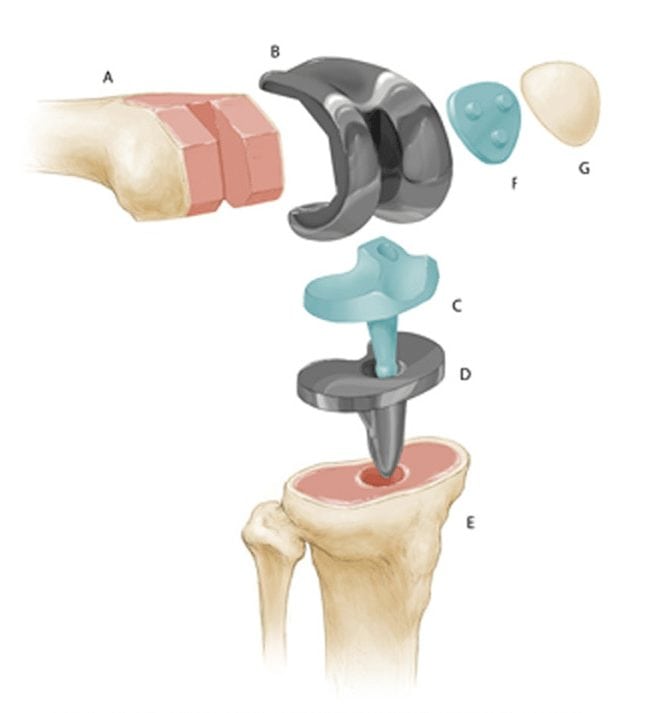

При полном эндопротезировании замене подлежат все три отсека, при частичном – только один из них. Большинство искусственных имплантатов состоят из четырех компонентов:

- Большеберцовый компонент. Плоский элемент, закрепляемый к верхней части голени. Изготавливается в виде металлической платформы с полиэтиленовой (пластиковой) вставкой. Материалом для изготовления — мягкий металл, например, титановый сплав.

- Бедренный компонент – крупная, изогнутая часть имплантата, закрепляемая в бедренной кости. Изготавливается из металла или керамики, чаще из прочных сплавов кобальта и хрома, потому что эта часть участвует в большинстве движений.

- Коленный компонент – куполообразная часть, заменяющая поврежденную коленную чашечку, трущуюся о бедренную кость. Используется не при всех видах суставной хирургии, изготавливается из полиэтилена (прочного пластика).

- Пластиковая прокладка. Располагается между большеберцовой и бедренной частью. Изготавливается из пластика (полиэтилена). Эта гибкая распорка обеспечивает гладкую, скользящую поверхность для обновленного коленного сустава, позволяет ему изгибаться и гнуться.